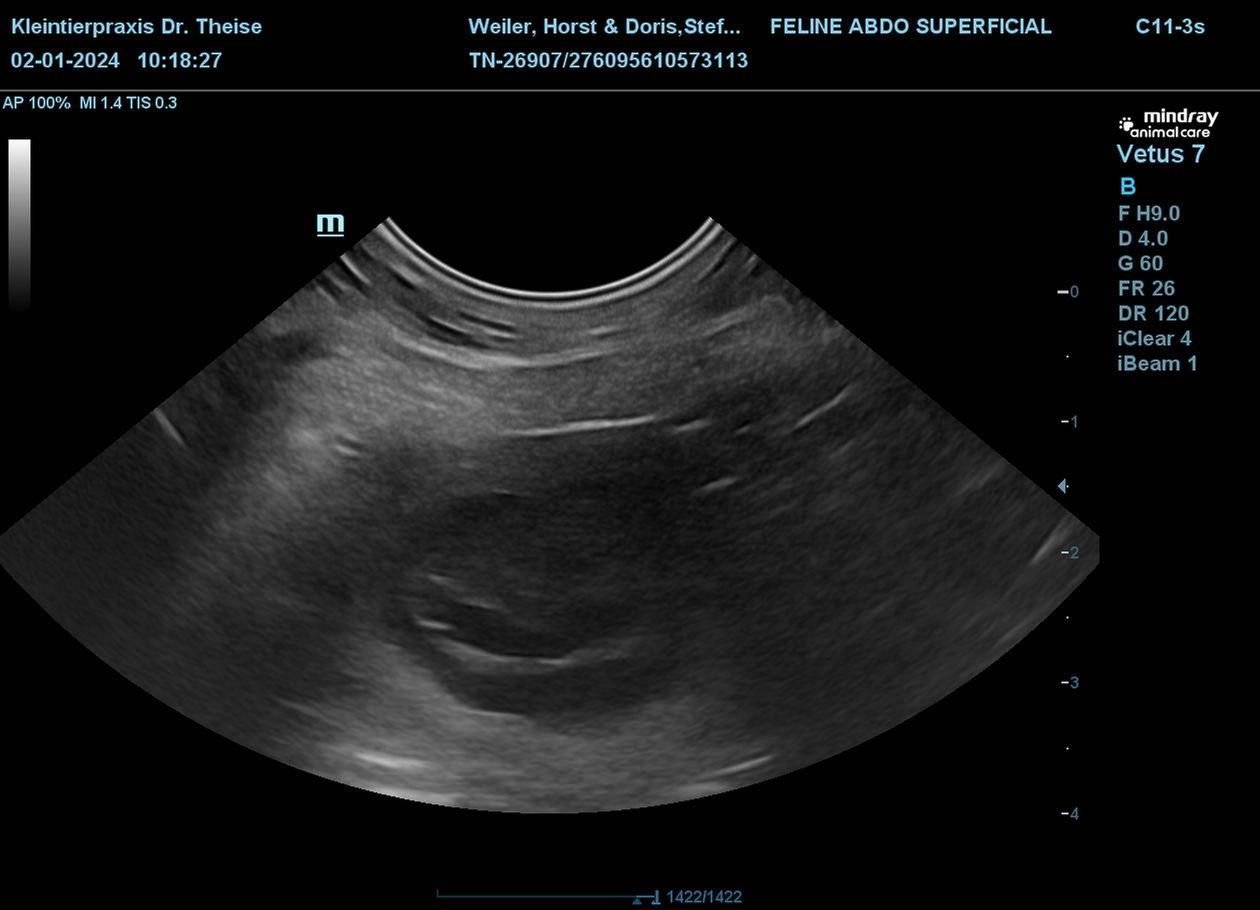

Nachdem der zweite Progesterontest grünes Licht gegeben hat sind wir am 03.12.2023 nach Bottrop aufgebrochen, wo sich die beiden Liebenden schnelle vereint haben, am 04.12.2023 wurde das ganze wiederholt. Und heute haben wir per Ultraschall das Ergebnis bekommen, Fleur ist belegt .